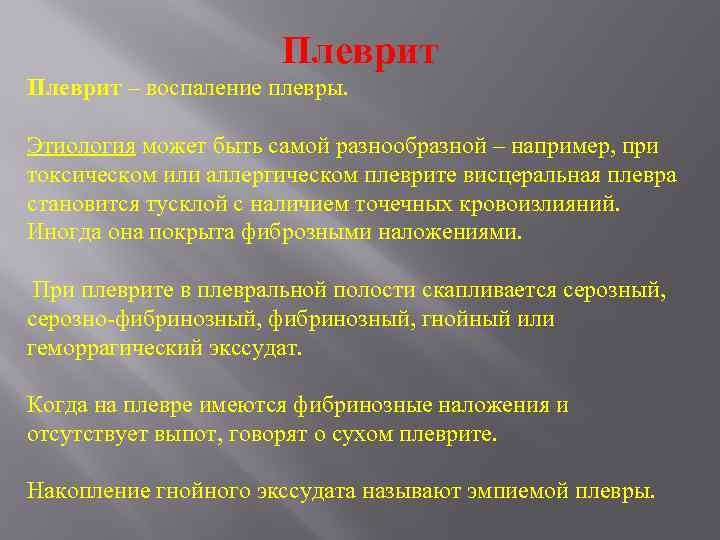

Дифференциальная диагностика заболеваний плевры